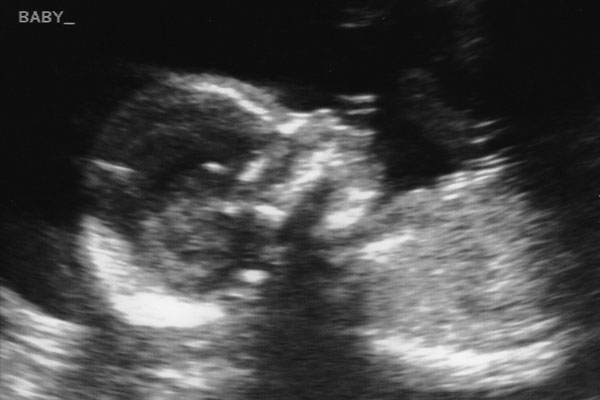

We had our second ultrasound appointment today at 18 weeks. Lindsey and I enjoyed getting to see our baby again. It was amazing to see how much he’s grown since our last ultrasound five weeks ago. Oh, did we mention it’s a he?

Tiny fingers.